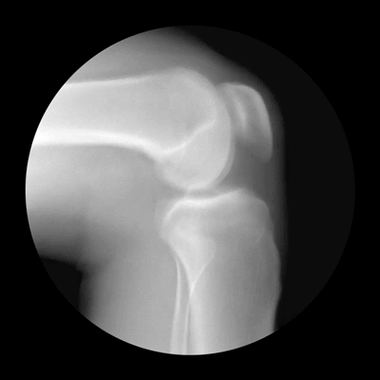

上下楼膝盖疼,平路没事,可能有髌骨软骨软化,教您两招自检_网易订阅

膝盖疼痛,可以吃软骨素吗? - 知乎

跑步后膝盖疼?如何防止跑步膝(附动图详解)_软骨

上下楼膝盖疼蹲起膝盖疼(上下楼蹲起就膝盖疼)

search results for: 膝盖肿胀 - 《默沙东诊疗手册大众版》

要想膝盖不疼,用到老,这份「膝盖使用手册」要收好 - 好网角收藏夹